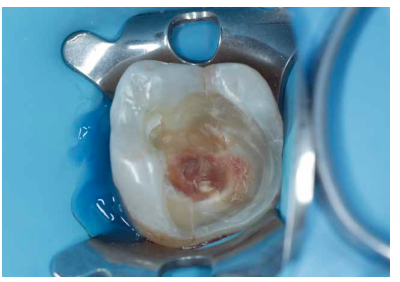

Se continuó con la remoción no selectiva de la caries y de la restauración previa con fresas redondas de turbina y contraángulo (Figura 3). Posteriormente, se expuso la pulpa en la zona más cercana a la lesión en una extensión de unos 2-3 mm con una fresa estéril redonda de diamante montada en turbina con abundante refrigeración. Se observó la pulpa y la sangre era roja brillante (Figura 4). Se controló el sangrado con una bolita de algodón embebida en hipoclorito de sodio 3% que se aplicó durante 2 minutos (Figura 5).